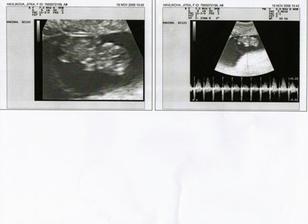

19.10 jsem na testíku našla //

27.10. Jdu navštívit pana doktora tak jsem zvědavá co mi poví a jestli už bude něco vidět🙂

26.1.2009 Tak Utz nám ukázal,že to bude holčička.Vážíme 287g.Tak stoho máme velkou radost a už se moc moc těšíme na tu naší